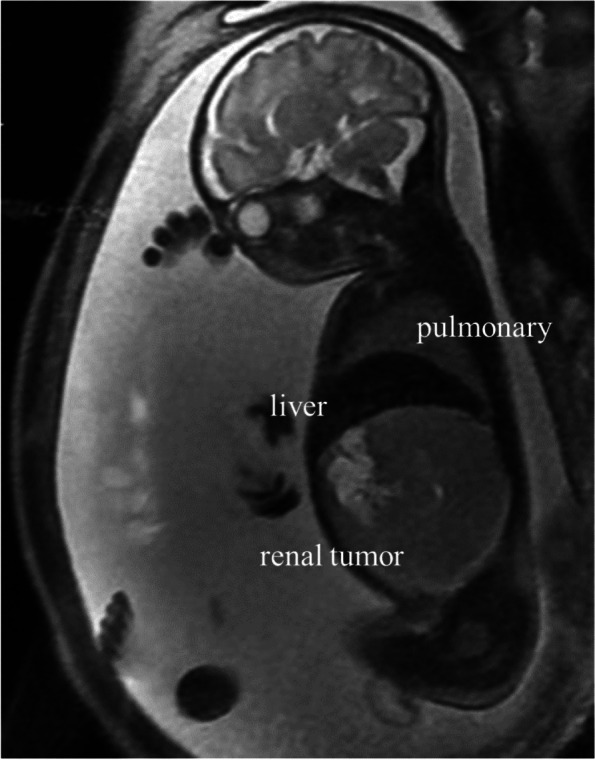

Fig. 1.

Fetal MRI at 32 weeks and 5 days of gestation. A 69 × 70 mm mass showing low signal on T1-weighted imaging and faint high signal on T2-weighted imaging was detected in the right kidney